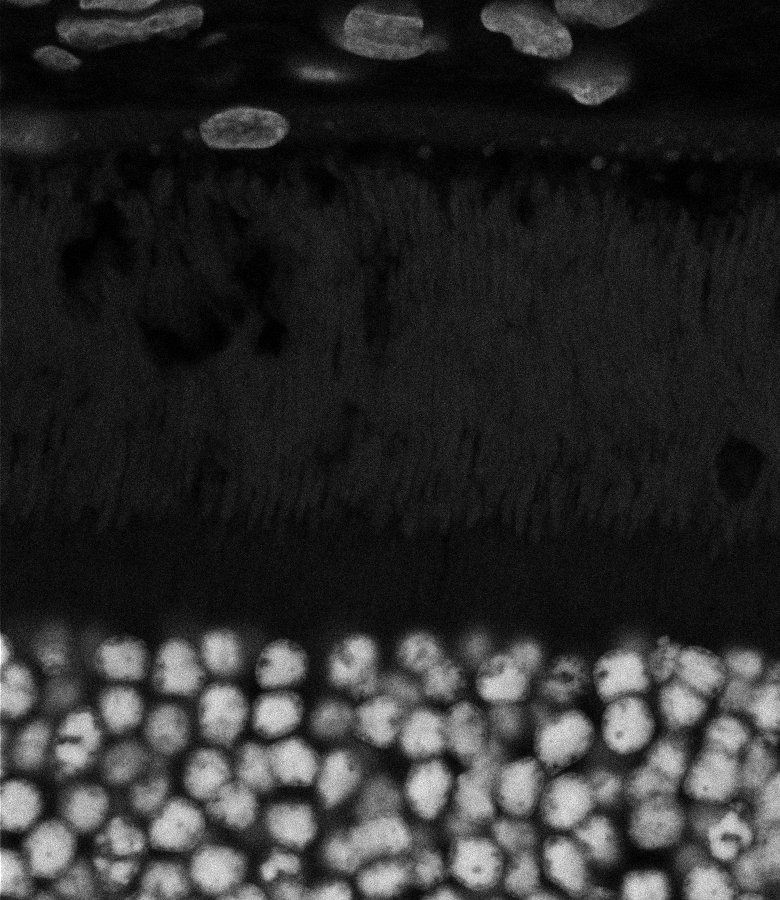

Healthy Retina

Unhealthy Retina